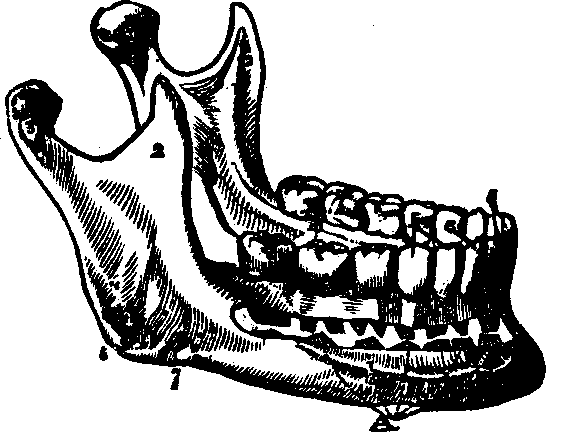

Fig. 26. A view of the lower jaw. 1. The body. 2, 2. Rami,

or branches. 3, 3. Processes of the lower jaw. m. Molar

teeth. b. Bicuspids, c. Cuspids. i. Incisors.